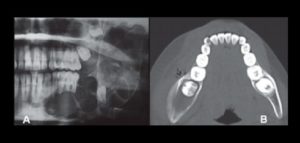

132 – Tratamiento de la reabsorción radicular interna idiopática perforante: controles radiográficos

La reabsorción radicular interna (RRI) es una afección inflamatoria que resulta en la destrucción progresiva de la dentina intra-radicular a lo largo de los tercios